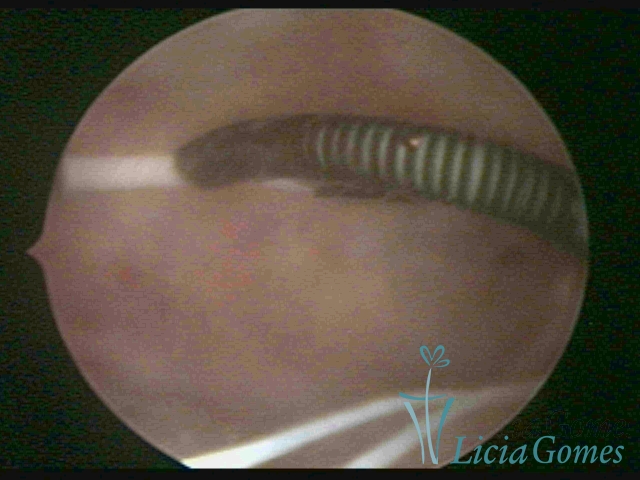

Myometrium punctured IUD